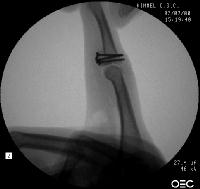

These wires are then replace, one at a time with micro screws.

The joint is approached through a volar "shotgun" hyperextension approach, as for a volar plate arthroplasty. In this case, the end of the profundus tendon is on the right, evidence of an old profundus avulsion injury.

Here, the graft is in place and the joint has been reduced. The proximal two screws were then backed out slightly, and the volar plate was secured with sutures looped around the proximal two screws, which were then tightened back (not shown).